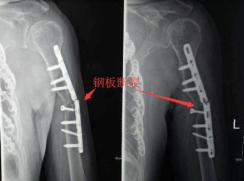

②内固定时间长

钢板在体内放置时间越长,周围骨痂牢固,以及由于器械产品更新换代的影响,容易造成螺钉滑丝、断钉的情况,增加创伤,因此建议不取。